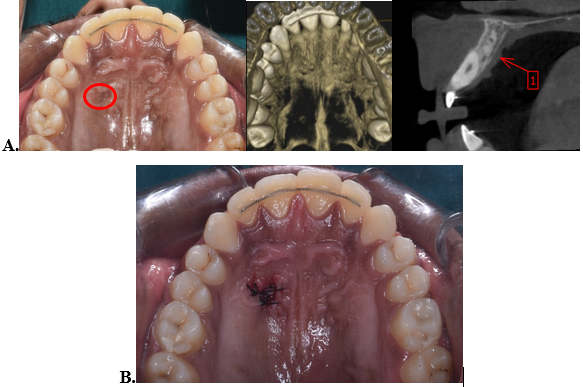

After six months, follow up was done, and the patient complained of unevenness of the soft tissues in the palatal implant site. A CBCT was advised for further investigation. The results of the investigation showed no abnormal skeletal findings. Soft tissue scarring was reported in the implant site. The patient was referred for periodontal therapy, and was advised for scar excision procedure to help promote proper healing of the implant site.

Also, during the investigation, an abnormal finding of localised periapical lesion near Canalis Sinuosus in the anterior maxilla was observed, which was diagnosed as idiopathic osteosclerosis. No intervention was planned.([Figure 6])

Mini-implants are frequently utilised in routine orthodontic treatment to improve the efficiency of orthopaedic or dental appliances. Mini-screws can have adverse effects and issues that might happen during their insertion, use, or removal. One such reported complication is disturbed wound healing or soft tissue scarring.[18] The palate is reportedly a safe zone with regard to scar formation. However, distinguishable scar like appearance of the tissue can frequently be observed after mini-screw removal.[19] Similarly, in our case, disturbed wound healing was reported with respect to the right palatal implant site. To address it and promote proper wound healing, surgical excision of the scar tissue was done.

Idiopathic osteosclerosis (IO), also called focal periapical osteopetrosis, is an intra bony, asymptomatic, benign, radiopaque lesion with unknown aetiology. The origin of IO may be associated as reaction to inflammation, occlusal trauma that might occur in tooth transition phase. IO usually develops early in life, and little changes occur after the affected individual is mature.[5] Normally, there is no requirement of any treatment. Some studies regarding orthodontic treatment and idiopathic osteosclerosis have reported delayed tooth movement in these areas,[20] while, a study conducted by Wang et al.[5] reported no obvious relation between idiopathic osteosclerosis and orthodontic treatment. In this case, the condition was diagnosed after treatment was completed and was benign with no symptoms, hence, no intervention was needed.